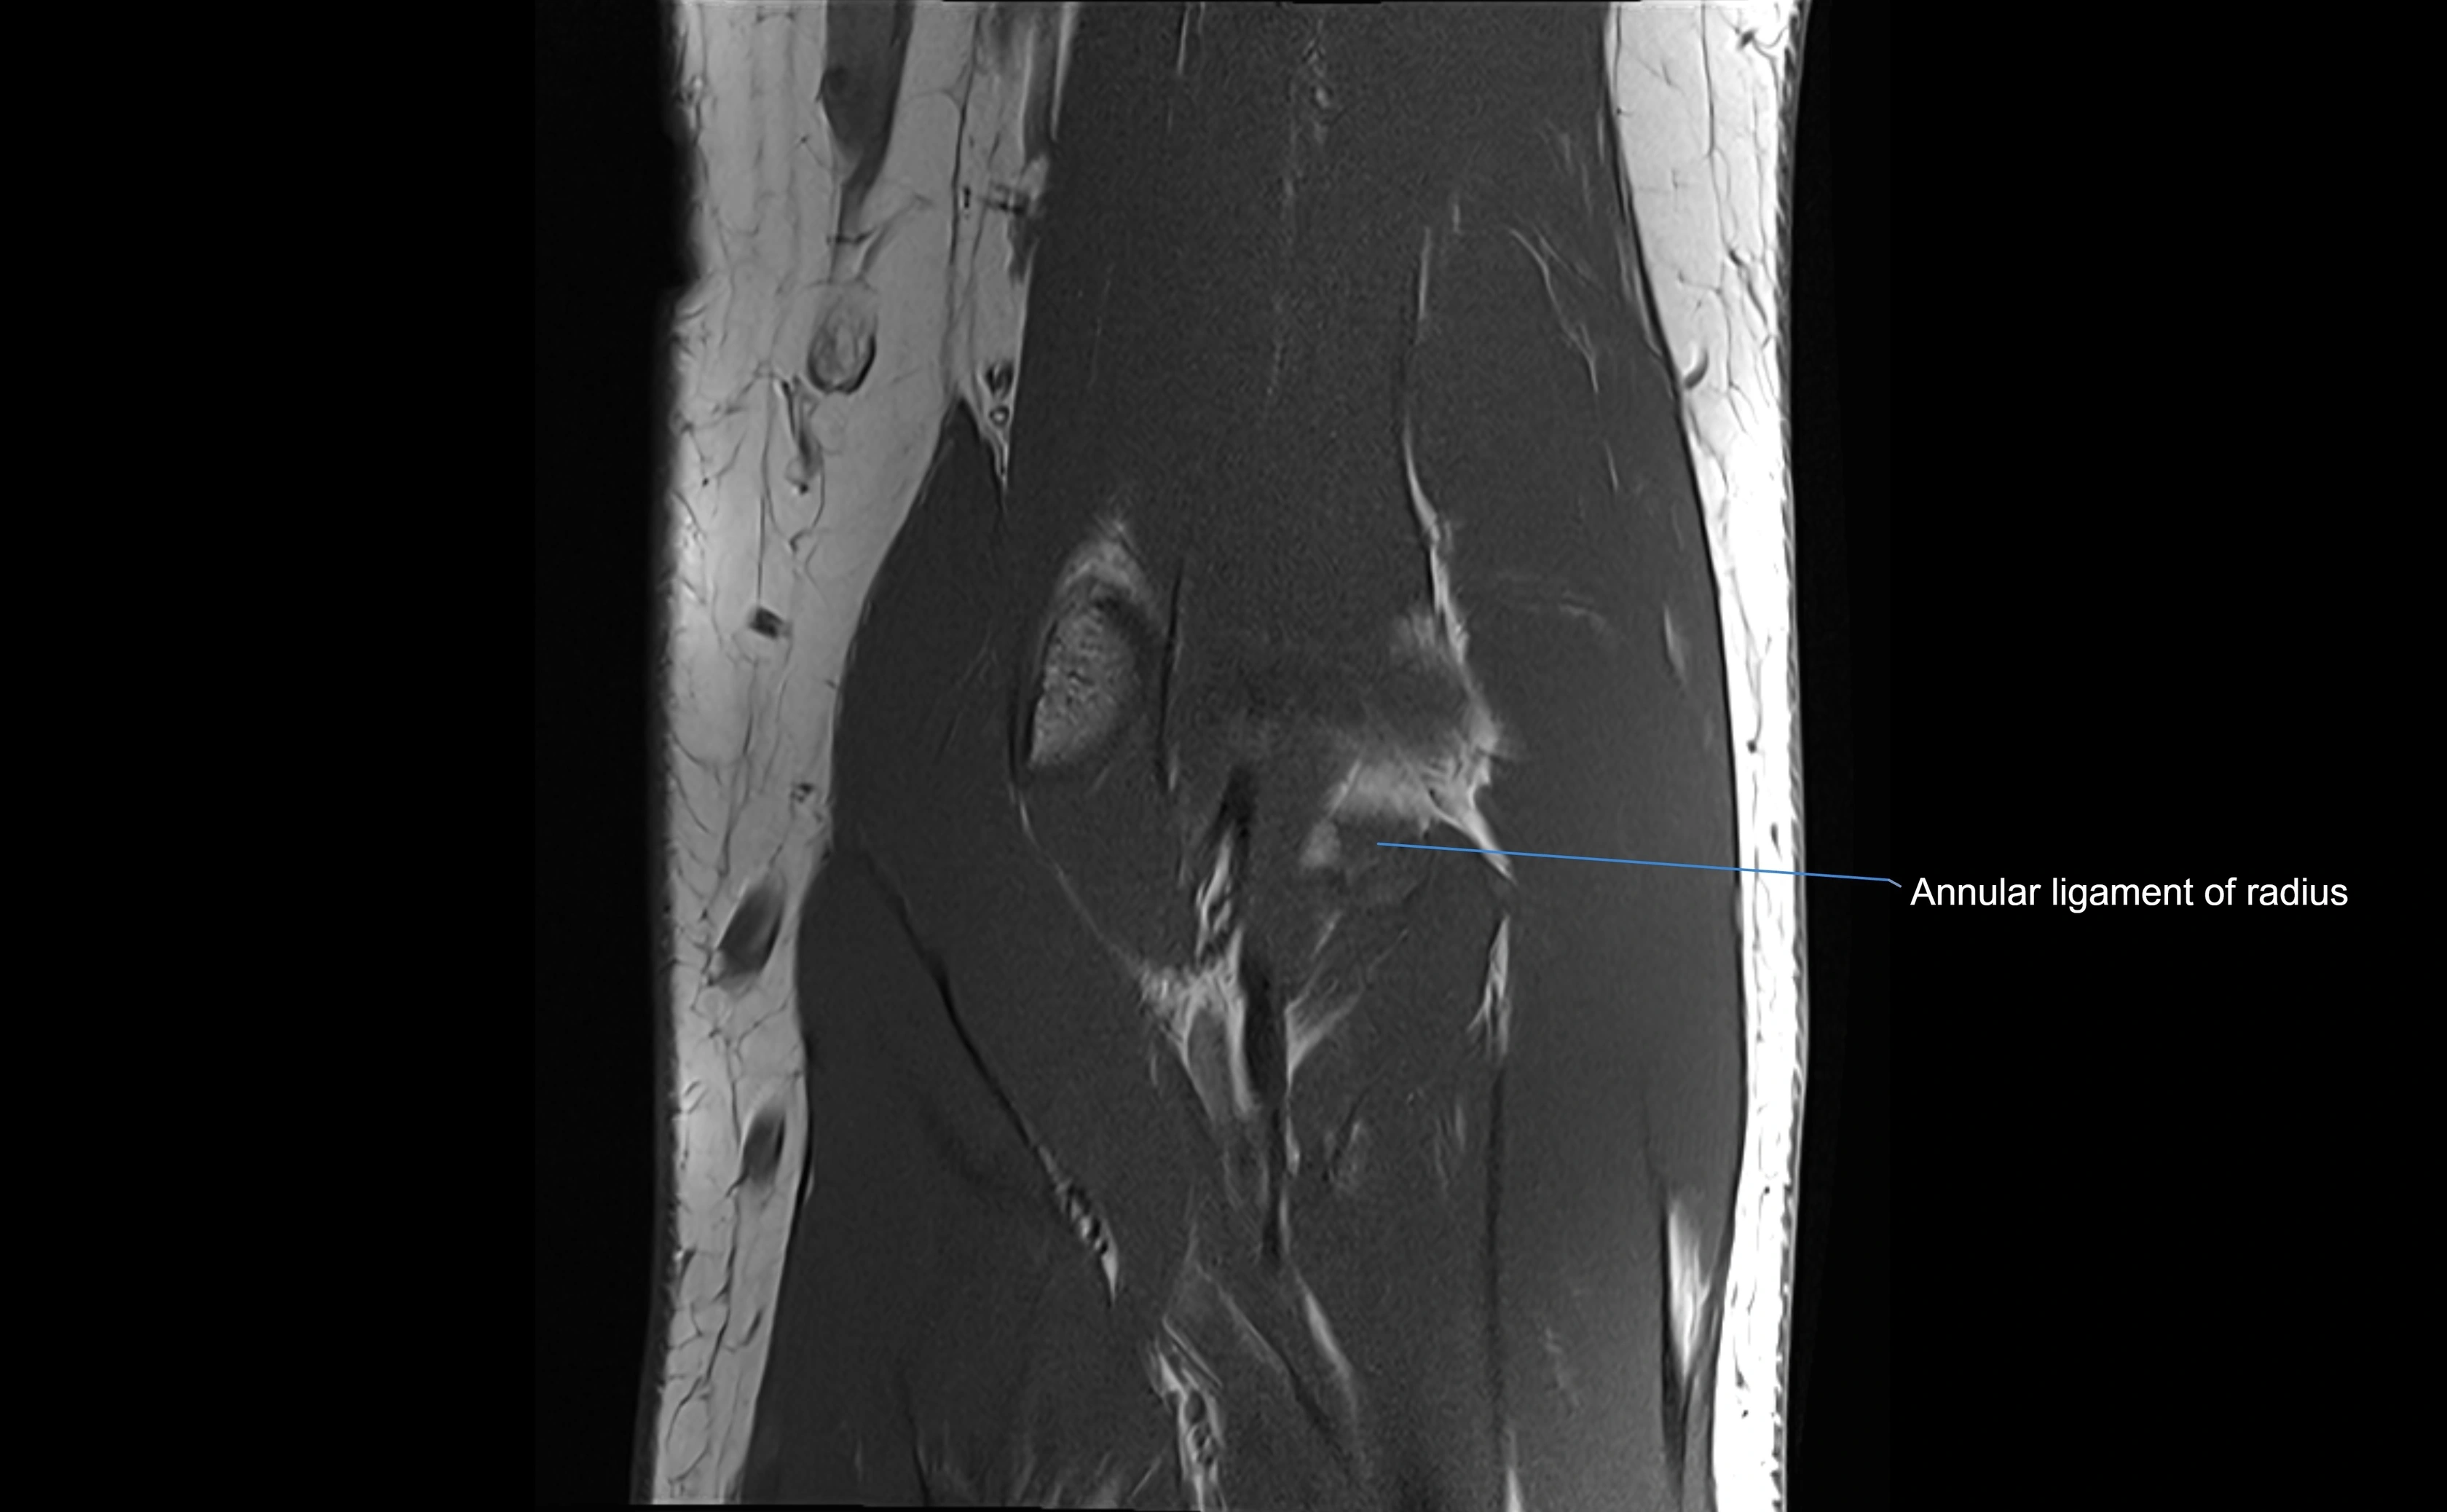

Annular ligament of radius

The annular ligament of the radius is a strong, circular band of fibers that encircles the head and neck of the radius, holding it securely against the radial notch of the ulna. It forms part of the proximal radioulnar joint, permitting smooth rotation of the radius during pronation and supination of the forearm.

The ligament acts like a collar or loop, maintaining radial head stability while allowing rotation. It is essential for forearm motion, elbow stability, and load transmission from the radius to the ulna and humerus.

Origin, Course, and Insertion

• Origin: Arises from the anterior margin of the radial notch of the ulna.

• Course: Forms a strong circular band that wraps around the radial head and neck, maintaining them within the radial notch.

• Insertion: Attaches to the posterior margin of the radial notch, completing a fibrous ring around the radial head.

• The inner surface of the ligament is lined with synovial membrane, allowing frictionless rotation.

MRI Appearance

MRI Arthrogram Appearance

• Contrast outlines the proximal radioulnar joint and radial head recess.

• Normal ligament appears as a dark ring surrounding the radial head, containing the injected contrast within the joint cavity.

• Partial tear: contrast extends along the ligament or beneath its fibers.

• Complete tear or subluxation: contrast extravasates around the radial head or ulna, indicating discontinuity.

CT Arthrogram Appearance

• Contrast fills the proximal radioulnar joint and outlines the radial head.

• Normal annular ligament: appears as a smooth, thin ring confining contrast to the joint space.

• Partial tear: contrast seeps beneath ligament or into adjacent soft tissues.

• Complete tear or dislocation: contrast extravasates around the radial neck or ulnar radial notch.

• Highly effective for evaluating joint congruency, ligament integrity, and subluxation when MRI is unavailable or contraindicated.